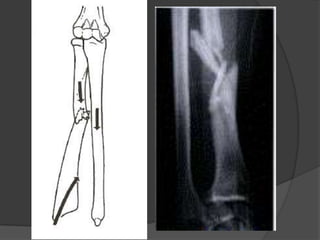

Este documento describe las lesiones de Monteggia y Galeazzi. La lesión de Monteggia implica una luxación de la articulación radio-húmeral-cubital asociada con una fractura del cubito, y se clasifica en 4 tipos. La lesión de Galeazzi implica una fractura del radio con acortamiento y luxación distal del cubito. El tratamiento para ambas lesiones depende de si es en niños o adultos, e involucra reducción y fijación con yeso o osteosíntesis.